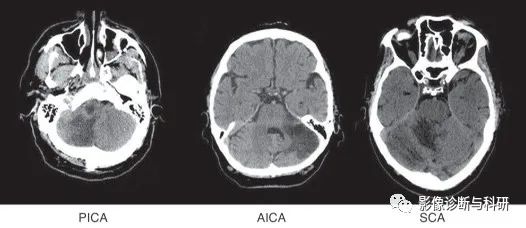

一、小脑动脉解剖

1.小脑上动脉(SCA):小脑上动脉为基底动脉的分支,主要营养小脑上面,即供应小脑半球上面、小脑蚓部上部、前髓帆等。

2.小脑下前动脉(AICA):小脑下前动脉主要营养小脑下面的前部,99%起源于基底动脉,但具体位置可有不同:75%起源于基底动脉下三分之一,16%起源于基底动脉中三分之一,9%与椎基底动脉连接。